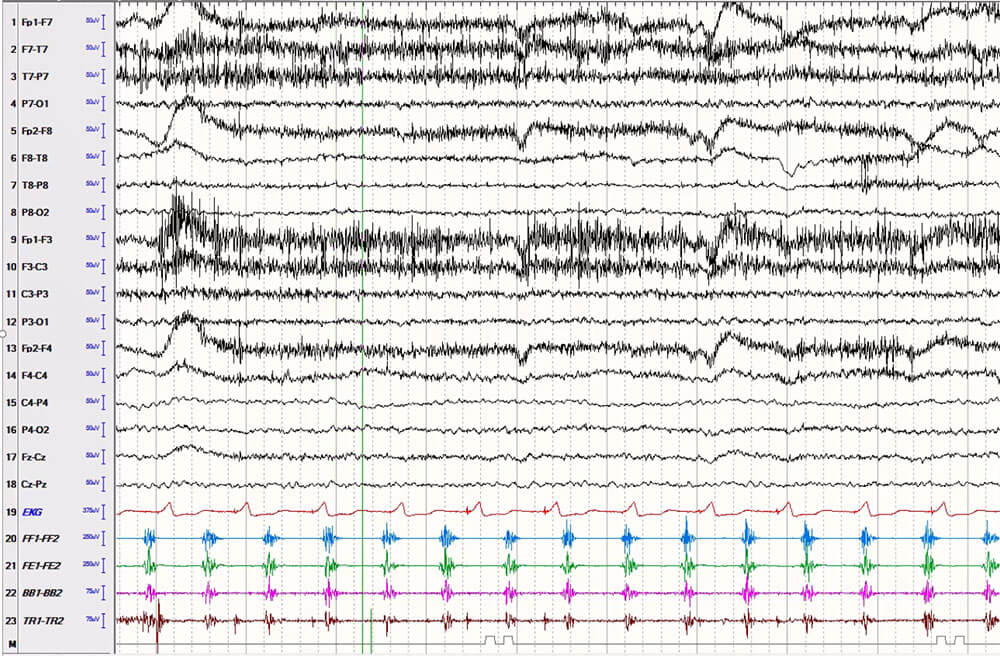

Dr. Fotedar and his colleagues retrospectively reviewed video-EEG recordings of 39 patients admitted to University Hospitals between 2016 and 2022 with clonic seizures to analyze the semiology and ictal EEG findings.

EEG-sEMG recording of a patient with right hand clonic seizure. The EEG (first 18 channels) does not show any discernible seizure pattern, but the sEMG channels (channel #20-23) show clear brief tetanic contractions, alternating with brief silent periods, synchronized between flexor and extensor muscle groups, consistent with a cortical/epileptic origin of the clonic movement. This sample shows the value of sEMG recording in analyzing patients with twitching movements, concerning for clonic seizures.I understand some photos were taken but may not have sufficient resolutionCaption: EEG-sEMG recording of a patient with right hand clonic seizure. The EEG (first 18 channels) does not show any discernible seizure pattern, but the sEMG channels (channel #20-23) show clear brief tetanic contractions, alternating with brief silent periods, synchronized between flexor and extensor muscle groups, consistent with a cortical/epileptic origin of the clonic movement. This sample shows the value of sEMG recording in analyzing patients with twitching movements, concerning for clonic seizures.

“As a Level 4 epilepsy center treating complex nonlesional epilepsy patients, we rely on seizure semiology to identify the epileptogenic zone as an essential component of presurgical planning,” he says. “Because we had both EEG and video recording of these patients’ seizures, we were able to analyze the simultaneous data and make correlations about where the clonic seizure originated and how it affected the body.”

The team also utilized surface electromyography processing (EMG) to gather additional recordings for 17 patients in the study. “We developed a protocol within the UH Epilepsy Center for how to place these electrodes to map muscle activation patterns in clonic seizures,” Dr. Fotedar says. “As far as I am aware, our study is the first and largest to report the surface EMG characteristics of this prevalent type of seizure.”